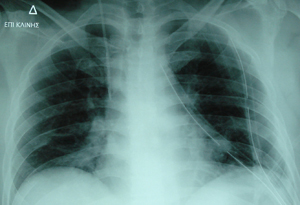

Εικόνα 5

Οπισθιοπρόσθια ακτινογραφία θώρακος, τρεις μέρες μετεγχειρητικά όπου

διακρίνονται οι δύο σωλήνες παροχέτευσης. Πλήρης έκπτυξη του αριστερού πνεύμονος.